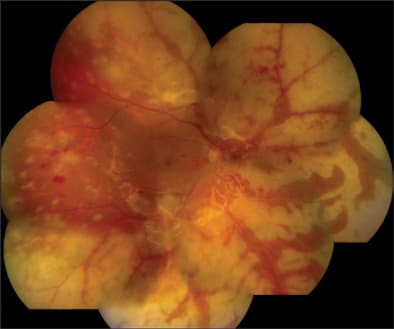

On postoperative day 2, the retinal lesions showed demarcation, suggesting regression of the active process (Figures 4 and 5). Her vision in OD had now declined to 20/600. Keratic precipitates were noted to regress in size and number. The retinal lesions continued to decrease over the course of the 10 days with a concomitant improvement of her vision to 20/400, so that we were comfortable to discharge the patient on oral acyclovir 800 mg 5 times per day. Acyclovir therapy was maintained over a total of 3 months. At 6 months postoperatively, we opted to remove the silicone oil during cataract surgery on her right eye. Subsequently, ocular hypotony developed in OD with choroidal detachments (Figure 6), which required a silicone oil refill. An aspirate from the vitreous cavity obtained during the latter procedure was again positive for V. zoster immunoglobulin A by immunofluorescence assay, which prompted us to resume oral acyclovir therapy with 400 mg 3 times per day, along with 8 mg prednisone po and prednisone ointment twice per day for her right eye.

Figure 4. Composite color fundus photo on postoperative day 2, showing demarcation of retinal lesions with a preserved macula and temporal midperiphery.